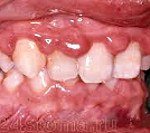

Гипертрофический гингивит. Воспалительные изменения тканей десны, сопровождающиеся их разрастанием (гипертрофией) с образованием ложных зубодесневых карманов, закрывающих зубную коронку. Клинические проявления гипертрофического гингивита характеризуются отечностью, жжением, гиперемией и кровоточивостью десен (при прикосновении, чистке зубов, во время еды), болевой реакцией на горячую, холодную или кислую пищу, неэстетичностью внешнего вида десны. Диагностика гипертрофического гингивита включает в себя осмотр и пальпацию десен, определение стоматологических индексов, проведение рентгенологического исследования. В лечении гипертрофического гингивита используется местная противовоспалительная терапия, склеротерапия, физиотерапия, диатермокоагуляция десневых сосочков, гингивэктомия.

Клинически при отечной форме гипертрофического гингивита больные помимо жалоб на кровоточивость десен при еде, при чистке зубов предъявляют жалобы на косметический дефект, связанный с увеличением объема десны. Гипертрофический гингивит при котором гипертрофия десны не превышает 1/3 длины коронки зуба называют легким. Гипертрофический гингивит средней тяжести характеризуется более выраженной деформацией десны – до 1/2 коронки зуба. при тяжелой – десна покрывает 2/3 или всю коронку зуба.

Объективно отечная форма гипертрофического гингивита характеризуется увеличением десны, глянцево-синюшной поверхностью, кровоточивостью при зондировании зубодесневой борозды, иногда при дотрагивании, образованием ложных зубодесневых карманов. Эпителиальные прикрепления не нарушены.

Отечная форма гипертрофического гингивита характеризуется жжением, болезненностью и кровоточивостью десен при чистке зубов и приеме пищи, гипертрофией межзубных сосочков, ярко-красным цветом десны. При стоматологическом осмотре обнаруживается увеличение и отечность десневых сосочков, их гиперемия с синюшным оттенком, глянцевый блеск, кровоточивость при зондировании; наличие зубных отложений. Типично образование ложных зубодесневых карманов, содержащих детрит. Целостность зубодесневого соединения при гипертрофическом гингивите не нарушена.